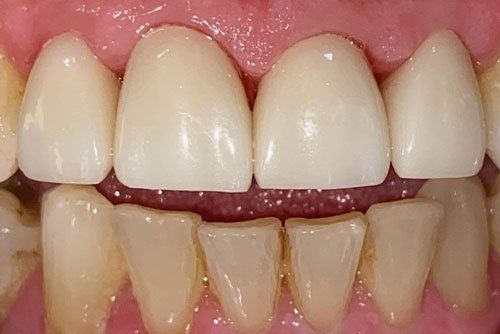

Dental Crowns Treatment

Ryan came to us with decay and breakage of his front teeth. We were able to restore and brighten up his smile! He left our office a new man! Ryan had no idea the results would be so dramatically different. He was thrilled with his brighter, healthier smile! Thank you Ryan for allowing us to take care of you!